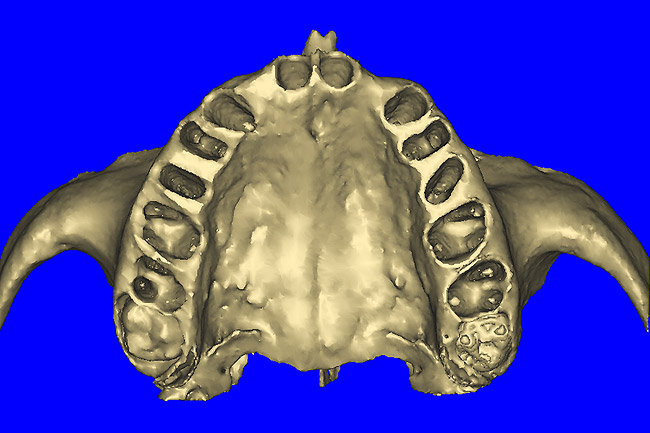

Using different masking (segmentation) and threshold Hounsfield unit values, several new 3D bone volumes can be created which offer invaluable information. To help determine the final position of each implant a new bone model was created with a Hounsfield unit value of 1480, which eliminated all but the densest objects included in the scan data. (Results may vary depending on the CBCT machine used.) The inner and outer layers of bone were removed, leaving the underlying enamel and root structure of the teeth (Figure 8A). After the bone had been stripped away, the root inclinations were examined closely. The most striking findings confirmed the rotated position of the right central, while revealing the slight mesial dilaceration of the root apex, which converged on the space needed for the path of the potential implant (Figure 8B). The schematic shapes of the proposed implants were visualized for the right and left lateral spaces in different rotations of the 3D maxillary arch. It was at this point that a determination was made as to the appropriate implant shape and type that would fit the available space while avoiding encroachment on adjacent tooth roots. A tapered design implant (Tapered Screw-Vent®, Zimmer Dental, www.zimmerdental.com) was chosen from the large virtual library. With the SIMPlant software, the virtual library contains data from dozens of implant manufacturers and realistic.computer-aided design representations as seen in Figure 9A through the translucent bone. The position of the left implant can be visualized with adequate mesial-distal distance between adjacent tooth roots (Figure 9B) and a more delicate placement (Figure 9C).

Figure 8a  By using the masking feature, the inner and outer layers of bone were removed virtually, revealing (A) the enamel and root structure of the teeth and the rotated position of the right central and (B) a slight mesial dilacerations of the root apex.

Figure 8a

Figure 8b  By using the masking feature, the inner and outer layers of bone were removed virtually, revealing (A) the enamel and root structure of the teeth and the rotated position of the right central and (B) a slight mesial dilacerations of the root apex.

Figure 8b